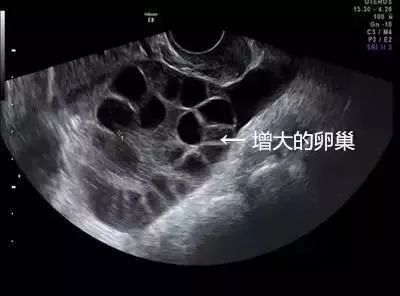

琳琳到浙江省这家妇幼保健院就诊,B超提示腹腔内大量积液,胸腔少量积液,卵巢增大超过3倍以上,考虑是卵巢过度刺激综合症,被收治住院。

1、卵巢过度刺激综合征,尤其是瘦小、年轻的女孩子更容易得。卵巢增大导致卵巢壁毛细血管通透性增大,体液积聚于组织间隙,进而使引起腹腔积液、胸腔积液,甚至会导致血栓,危害生命。